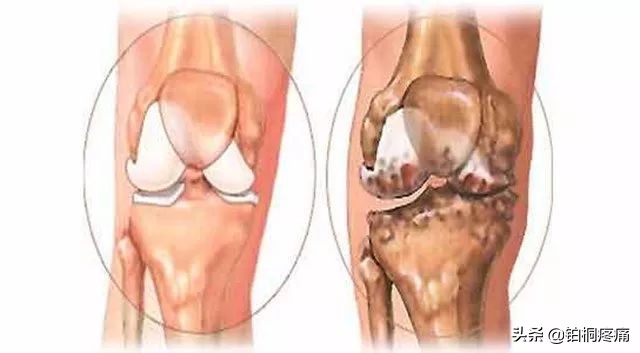

01、骨关节炎

中老年人常出现膝盖红肿痛、上下楼梯痛、坐起立行时膝部酸痛等不适,在休息后缓解。如果拍片子发现关节磨损、骨质增生、关节间隙变狭窄,甚至出现关节畸形,说明膝关节退化到了骨关节炎的阶段,已经不可逆转,需要引起重视。轻者可采取康复、止痛治疗,稍严重者可进行疼痛科专有微创介入治疗。